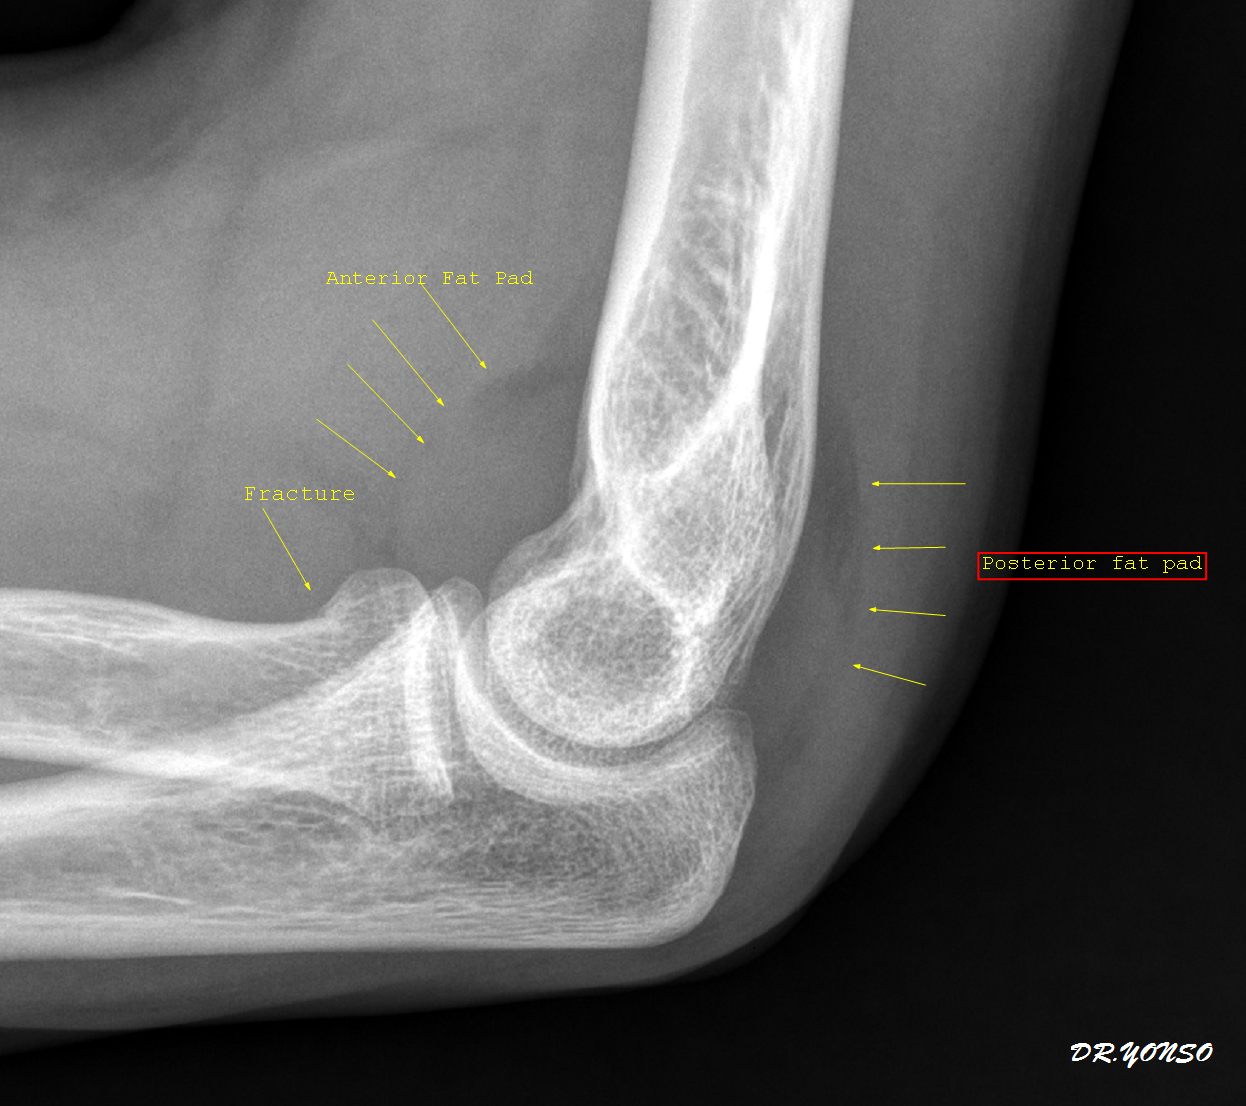

Struggling with persistent Tendonitis In Elbow? Discover effective treatments, proven relief techniques, and recovery exercises to manage tennis or golfer’s elbow. Our expert guide helps you identify common symptoms, understand underlying causes, and find the best physical therapy strategies to reduce inflammation, alleviate chronic joint pain, and restore full range of motion for a faster, pain-free recovery.